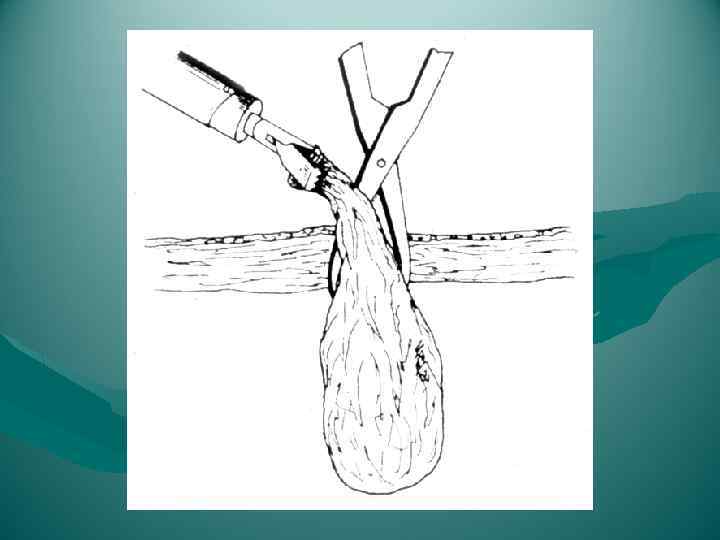

Перевязка левой печеночной вены.

Перевязка левой печеночной вены.

Холецитэктомия от шейки

Холецитэктомия от шейки